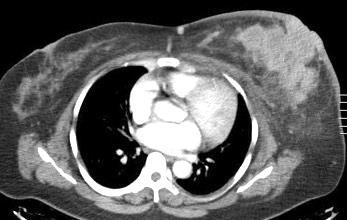

Masa axilar izquierda y derrame pleural derecho. Implantes pleurales, paraespinales . Ganglios en mamaria interna. Linfoma B difuso

Linfoma NH de cél. B. Invasión Transtorácica.

Afectación axilar